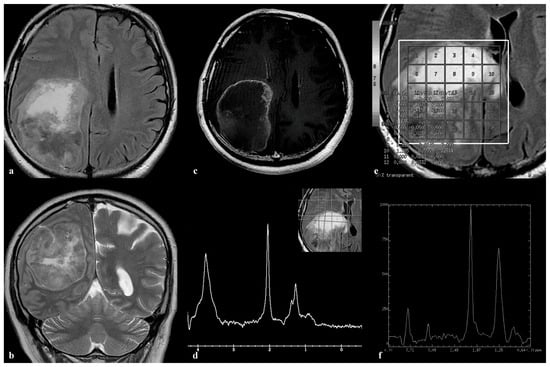

3.3. Patient 3